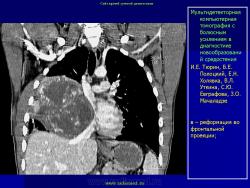

Средостение.  "Опухолевый рост".